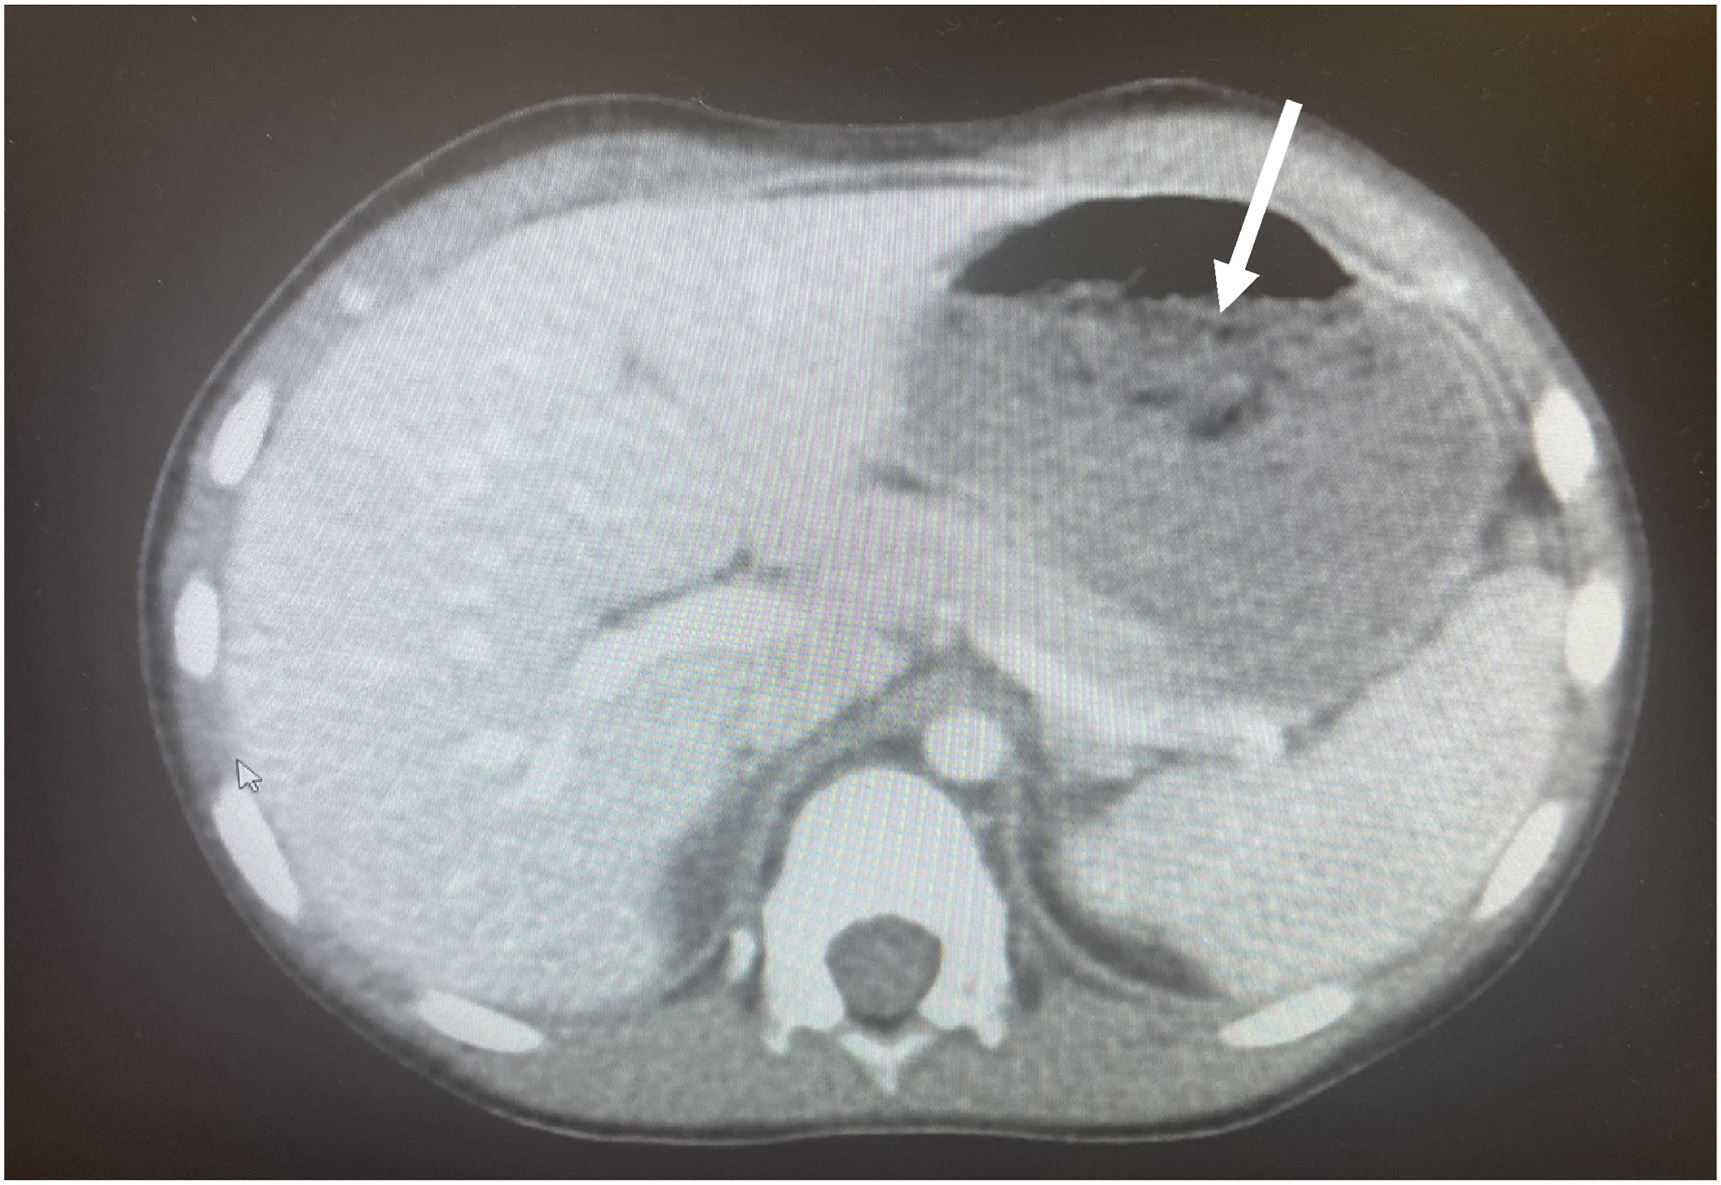

Ekoran itu, pasukan doktor yang diketuai oleh Dr. Chizite Iheonunekwu di Klinik Cleveland mula melakukan prosedur pembedahan dan menarik keluar gumpalan gula-gula menerusi kerongkong beliau.

Jelas doktor, gumpalan gula-gula yang disebut sebagai bezoar tersekat pada perut kanak-akanak ini hingga mengambil kira-kira 25 peratus ruang.

Dengan menggunakan skop khas, doktor kemudian mengeluarkan gumpalan berkenaan melalui esofagus atau kerongkong. Prosedur itu terpaksa dilakukan berulang kali bagi mengeluarkan kesemua gula-gula getah yang tersumbat.